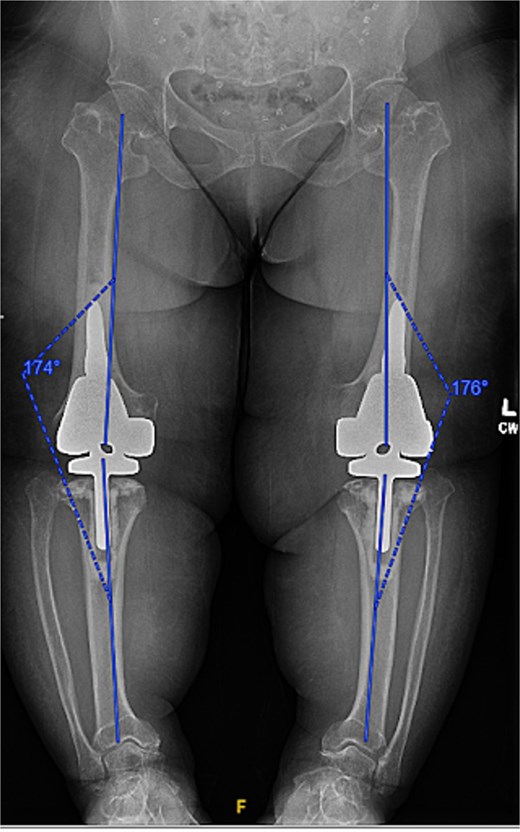

Given the severity of the coronal deformity, ligamentous laxity, and the patient’s functional limitations, the decision was made to proceed with simultaneous bilateral robot-assisted TKA using constrained prostheses. Using robotic-assisted navigation (Stryker Mako™), bony landmarks and soft tissue gaps were registered on the right knee. Initial preparation for a posterior-stabilized implant demonstrated profound lateral laxity after medial releases, prompting intraoperative conversion to a rotating-hinge design. A size XS femoral component and pediatric all-polyethylene tibial component (8 mm) were cemented, followed by hinge assembly. A similar approach was used for the left knee as severe medial compartment collapse and lateral laxity again necessitated the use of a rotating-hinge construct. The femur was prepared for an extra-small femoral component with a 12 × 50 mm cemented stem, and a size 8 mm pediatric all-polyethylene tibial component was implanted. The post-operative mechanical axis for the left and right knees were 4 and 6 degrees, respectively (Fig. 2).

Immediate postoperative AP radiographs following bilateral robot-assisted rotating-hinge TKA, showing well-aligned prosthetic components and correction of the coronal deformity. The post-operative mechanical axis for the left and right knees were 4 and 6 degrees, respectively.